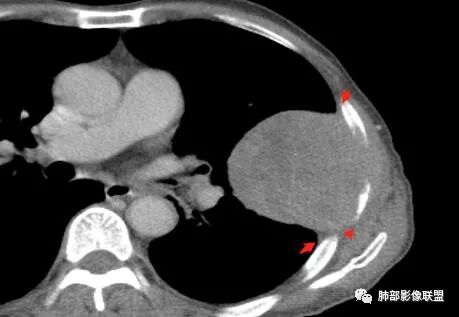

老年男性,外伤入院,“左上肺”实性肿块,边缘光滑,突破壁层胸膜并侵犯肋骨及肋间肌,增强扫描轻度强化,可见明显坏死。

• 胸CT:左肺上叶实性占位,病灶与支气管无关,病灶对斜裂挤压,病灶周围光滑,未见分叶、毛刺;纵隔窗可见病灶内低密度区,病灶对胸壁侵袭,并可见肋骨破坏。

胸CT:左上肺实性大肿块,边缘光滑,突破胸膜侵犯肋骨及肋间肌,纵隔淋巴结肿大,增强呈轻度强化,可见明显片状坏死。

胸部CT所见左肺上叶尖后段胸膜下较大山丘形肿块,边界清楚,宽基底与胸膜相贴,边缘与胸膜呈直角及锐角相交。邻近上叶尖后段支气管受压推挤,叶裂局部膨隆,病灶周围见少许磨玻璃密度影,边界不清。纵膈窗显示,肿块密度均匀,增强扫描呈不均匀轻度强化,邻近肋骨骨质破坏,病变沿肋间隙向外侵犯,局部胸膜增厚。纵膈内见多发小淋巴结,未见胸腔积液征象。综合考虑恶性占位,肉瘤样癌可能性大。腰椎及髋部考虑骨转移。

鳞癌因为侵袭性力较强,容易直接侵犯胸膜、胸壁,而周围型肺癌侵犯胸壁的90%癌肿是鳞癌,这也是鳞癌的一个特征性表现。邻近胸壁的脂肪层消失,胸壁肿块形成或有肋骨皮髓质边界不清的侵蚀破坏(而非边缘硬化或崩解)是瘤体向周围直接侵犯的可靠征象。

鳞癌因为破坏力强,其内可见灶样坏死区,坏死边界不清,其内血管破坏彻底。